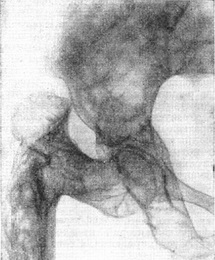

Нерідко, крім веретеноподібних деформацій, виникають деформації статичного характеру, чому сприяє знижена міцність кісток. В результаті подібного роду деформацій відбувається дугоподібне викривлення трубчастих кісток, а вхід у малий таз звужується настільки, що може прийняти вигляд так званого карткового серця (рис. 3). Особливо характерна деформація стегна, приймає вигляд так званої пастушої палиці (рис. 4), і деформація ребер, додає грудній клітці зовнішню схожість з формою дзвони.

![]() Рис. 3. Деформація таза при паратиреоидной остеодистрофії; звуження входу в малий таз у вигляді «карткового серця». Рис. 4. (праворуч) Характерна картина деформації стегнової кістки у вигляді «пастушої палиці» при паратиреоидной остеодистрофії. |